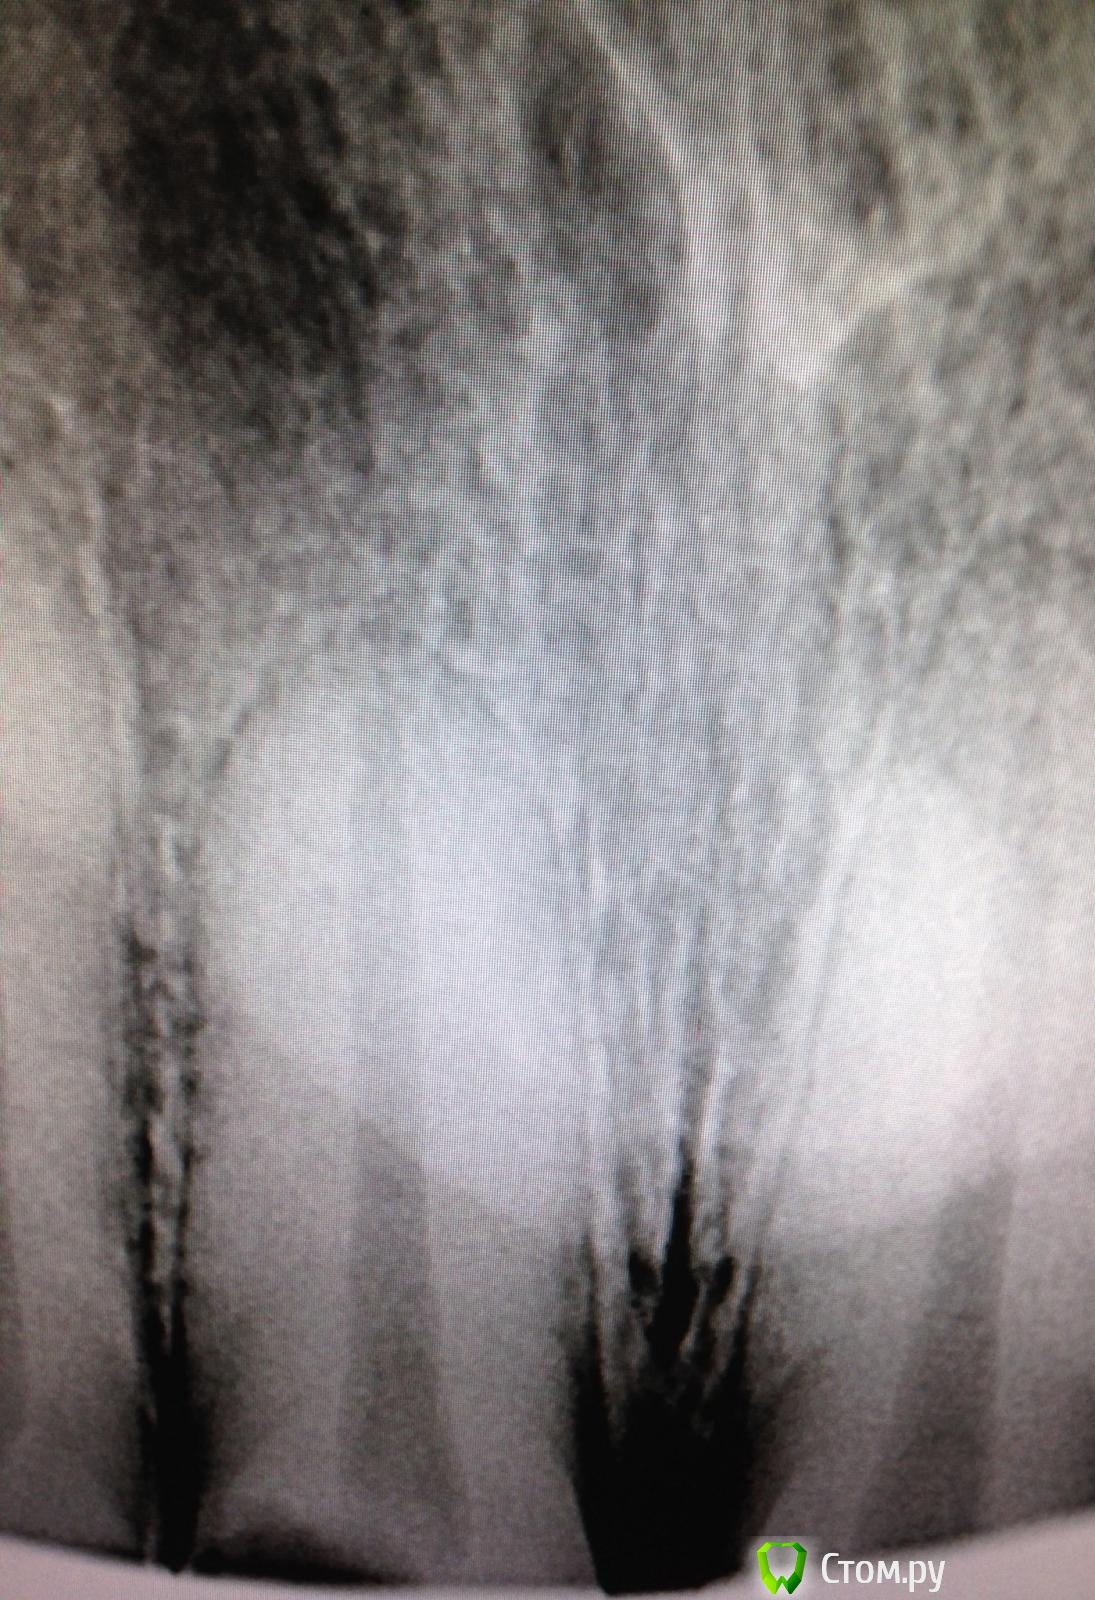

SSTi Опубликовано 7 октября, 2014 Автор Поделиться Опубликовано 7 октября, 2014 Как я не люблю широкие каналы! Понял это сегодня. 11. Сломан зуб давно. Болел. Потом не болет и тд. Стандартно. Весь в зарослях из десны. Сделали снимок. Ну, думаю, широкий и широкий. Ну и круто.Убрал десну. Феррул есть. Одел коффер. Преп. Вскрыли полость - там труп пульпы выглядывает и машет. Убрал эту красоту. Помылся. Померился. Машинными файлами посреб стенки, но толку мало. Начал делать уступ - 50 маленький. 55 мал. 60 мал, 70 мал. 80 - и тут я хоть уперся чуточку. Сделал упор как смог. Еще вымылся (мылись час в общей сложности). Латералка. Вот лучше бы семерку полечил, чем такую единицу. 1 Ссылка на комментарий

SSTi Опубликовано 7 октября, 2014 Автор Поделиться Опубликовано 7 октября, 2014 П.с. Был в шоке от гутты. 80 номер торчал из линейки калибровойной на 3.5 мм примерно. Как так то??? Ссылка на комментарий